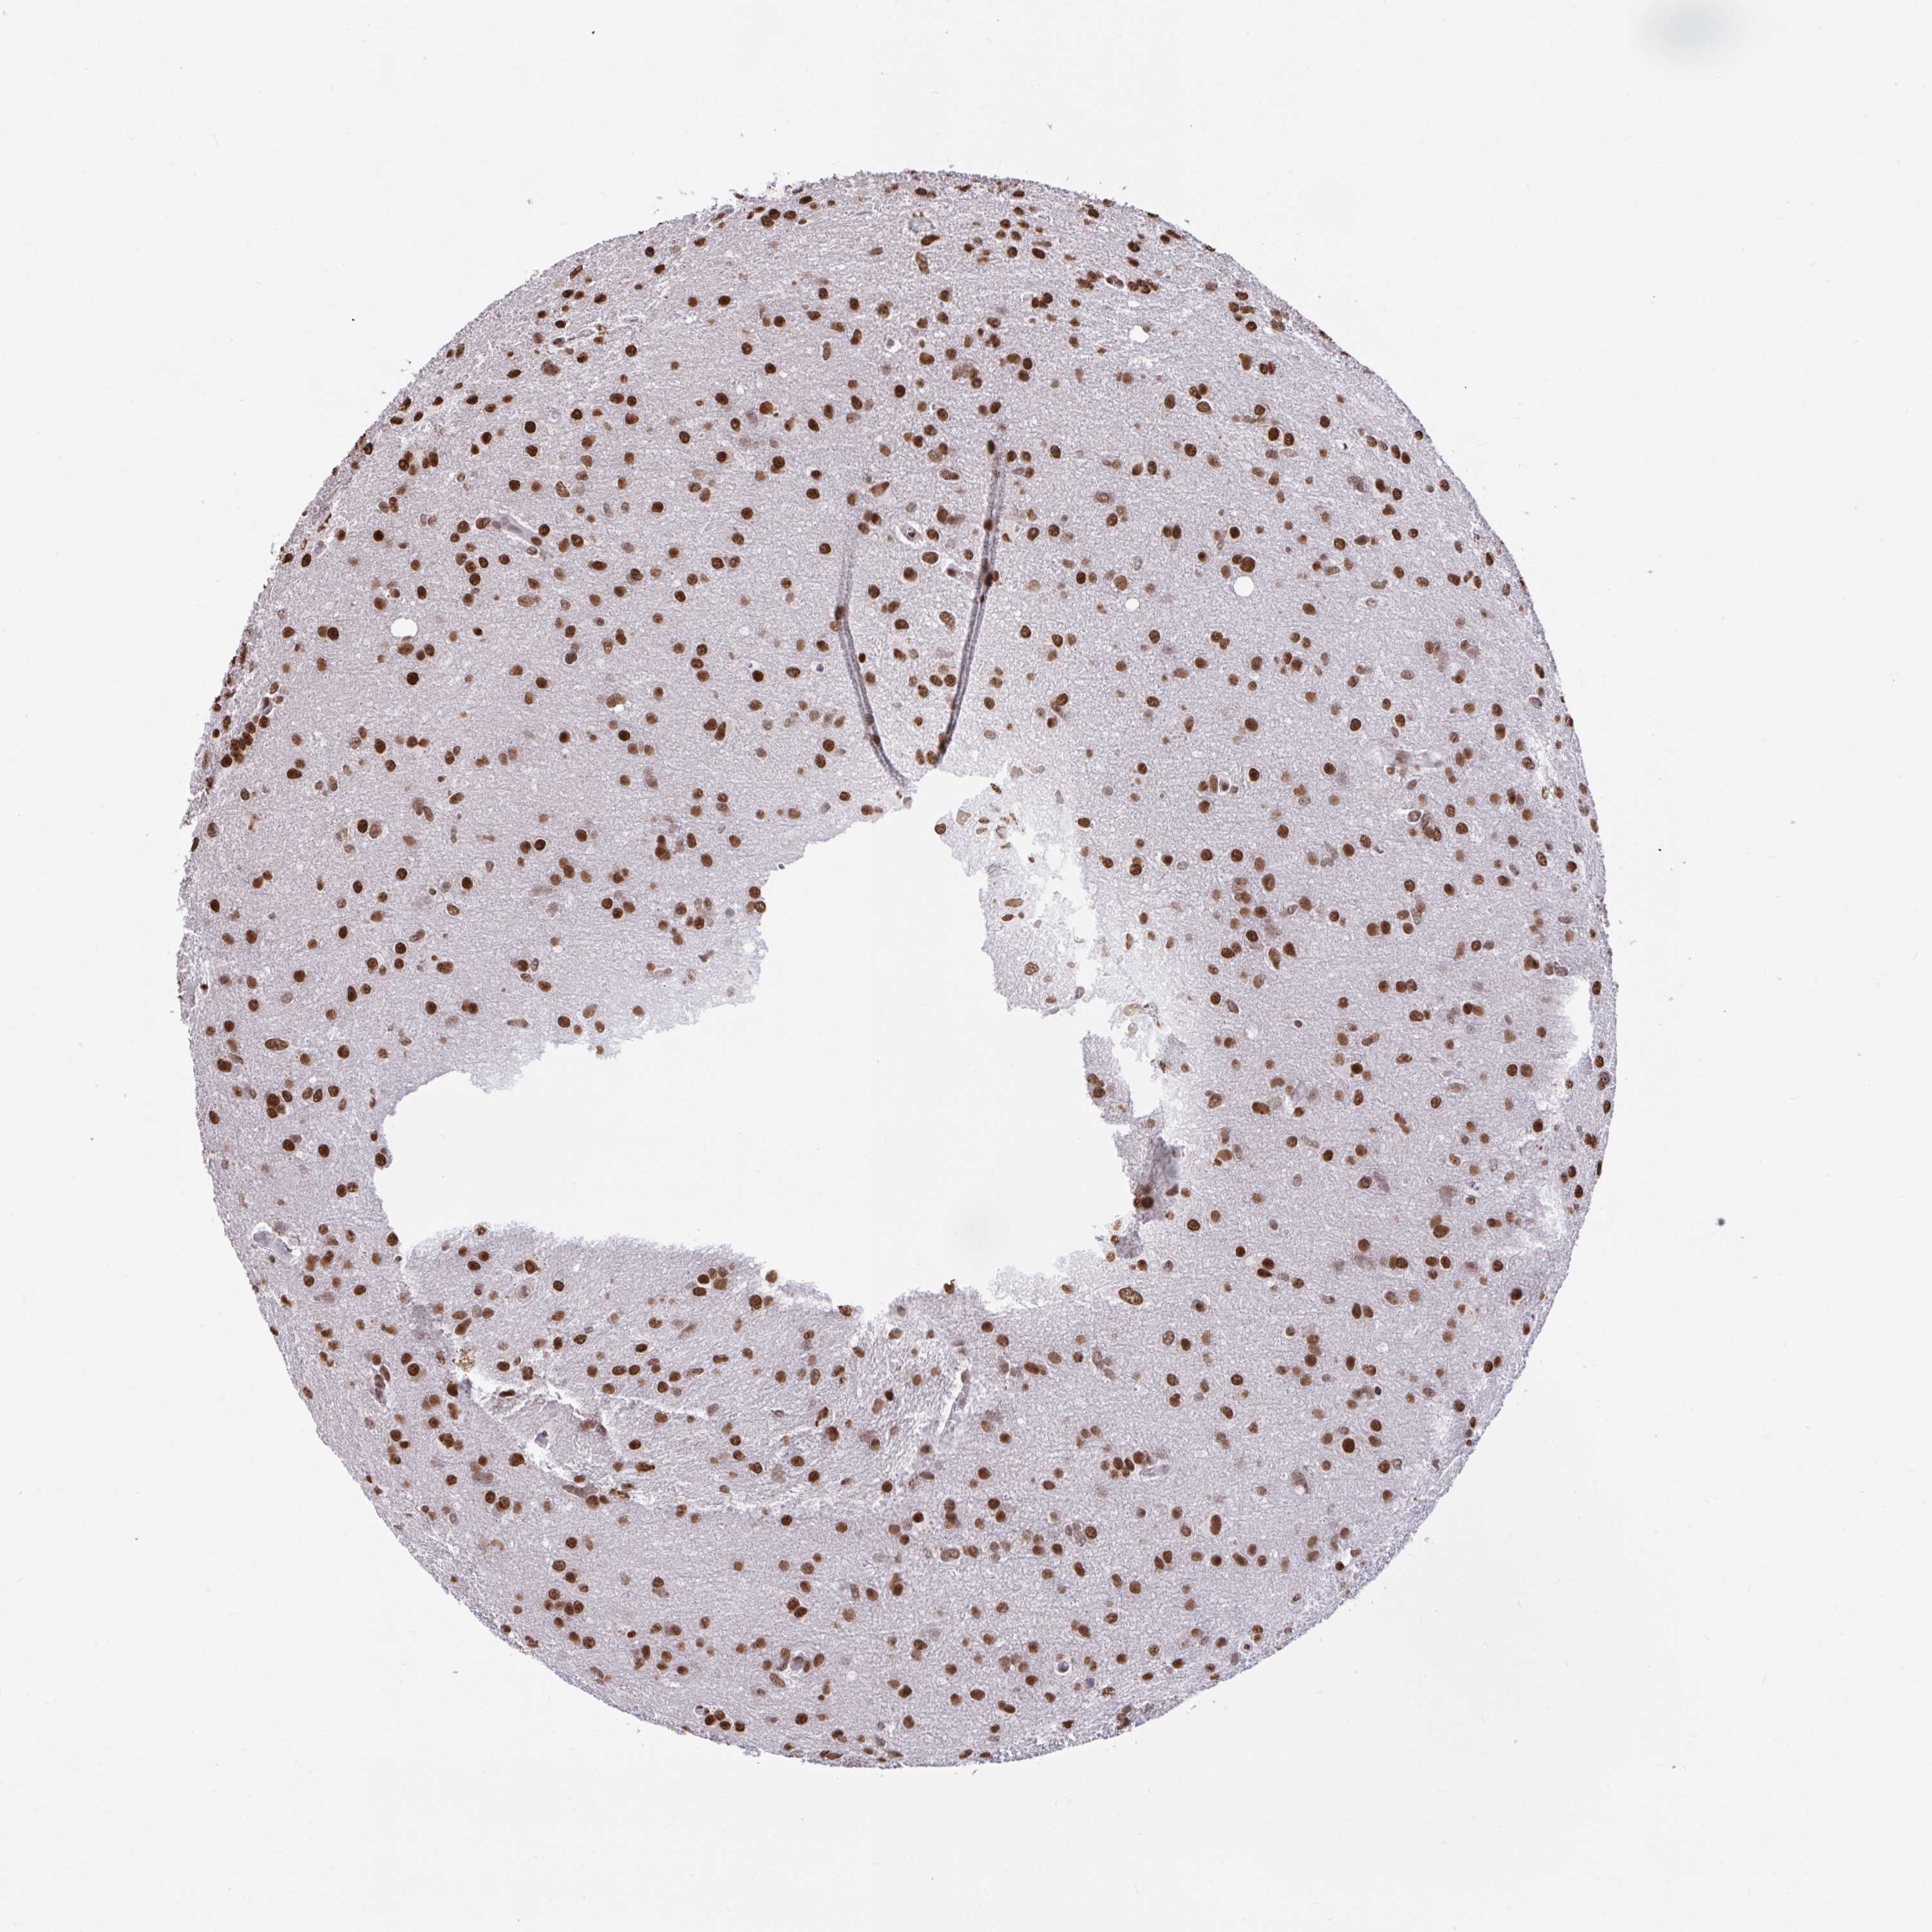

GLIOMA - Protein expressioni

A mouse-over function shows sample information and annotation data. Click on an image to view it in a full screen mode. Samples can be filtered based on level of antibody staining by selecting one or several of the following categories: high, medium, low and not detected. The assay and annotation is described here.

Note that samples used for immunohistochemistry by the Human Protein Atlas do not correspond to samples in the TCGA dataset.

Antibody stainingi

Antibody staining in the annotated cell types in the current human tissue is reported as not detected, low, medium, or high, based on conventional immunohistochemistry profiling in selected tissues. This score is based on the combination of the staining intensity and fraction of stained cells.

Each image is clickable and will lead to virtual microscopy that enables deeper exploration of all samples and also displays staining intensity scores, fraction scores and subcellular localization as well as patient and tissue information for each sample.

Antibody HPA056820

Antibody HPA063147

Staining

High

Medium

Low

Not detected

Intensity

Strong

Moderate

Weak

Negative

Quantity

>75%

75%-25%

<25%

None

Location

Nuclear

Cytoplasmic/membranous

Cytoplasmic/membranous,nuclear

Glioma, malignant, Low grade

Glioma, malignant, High grade